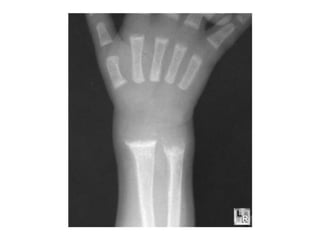

• Rickets is deficient mineralization at the growth plate of long bones,

resulting in growth retardation. If the underlying condition is not

treated, bone deformity occurs, typically causing bowed legs and

thickening of the ends of long bones.

• Only occurs in growing children before fusion of the epiphyses,

typically affecting wrists, knees, and costochondral junctions.